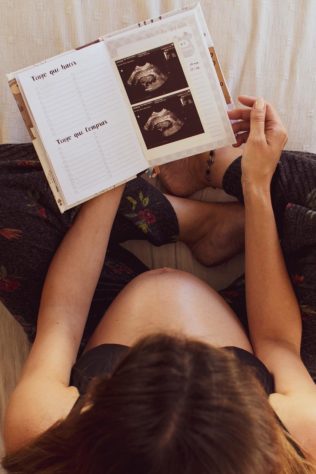

Tecnologia 3D encanta ao mostrar bebê em formação

Tecnologia 3D encanta ao mostrar bebê em formação